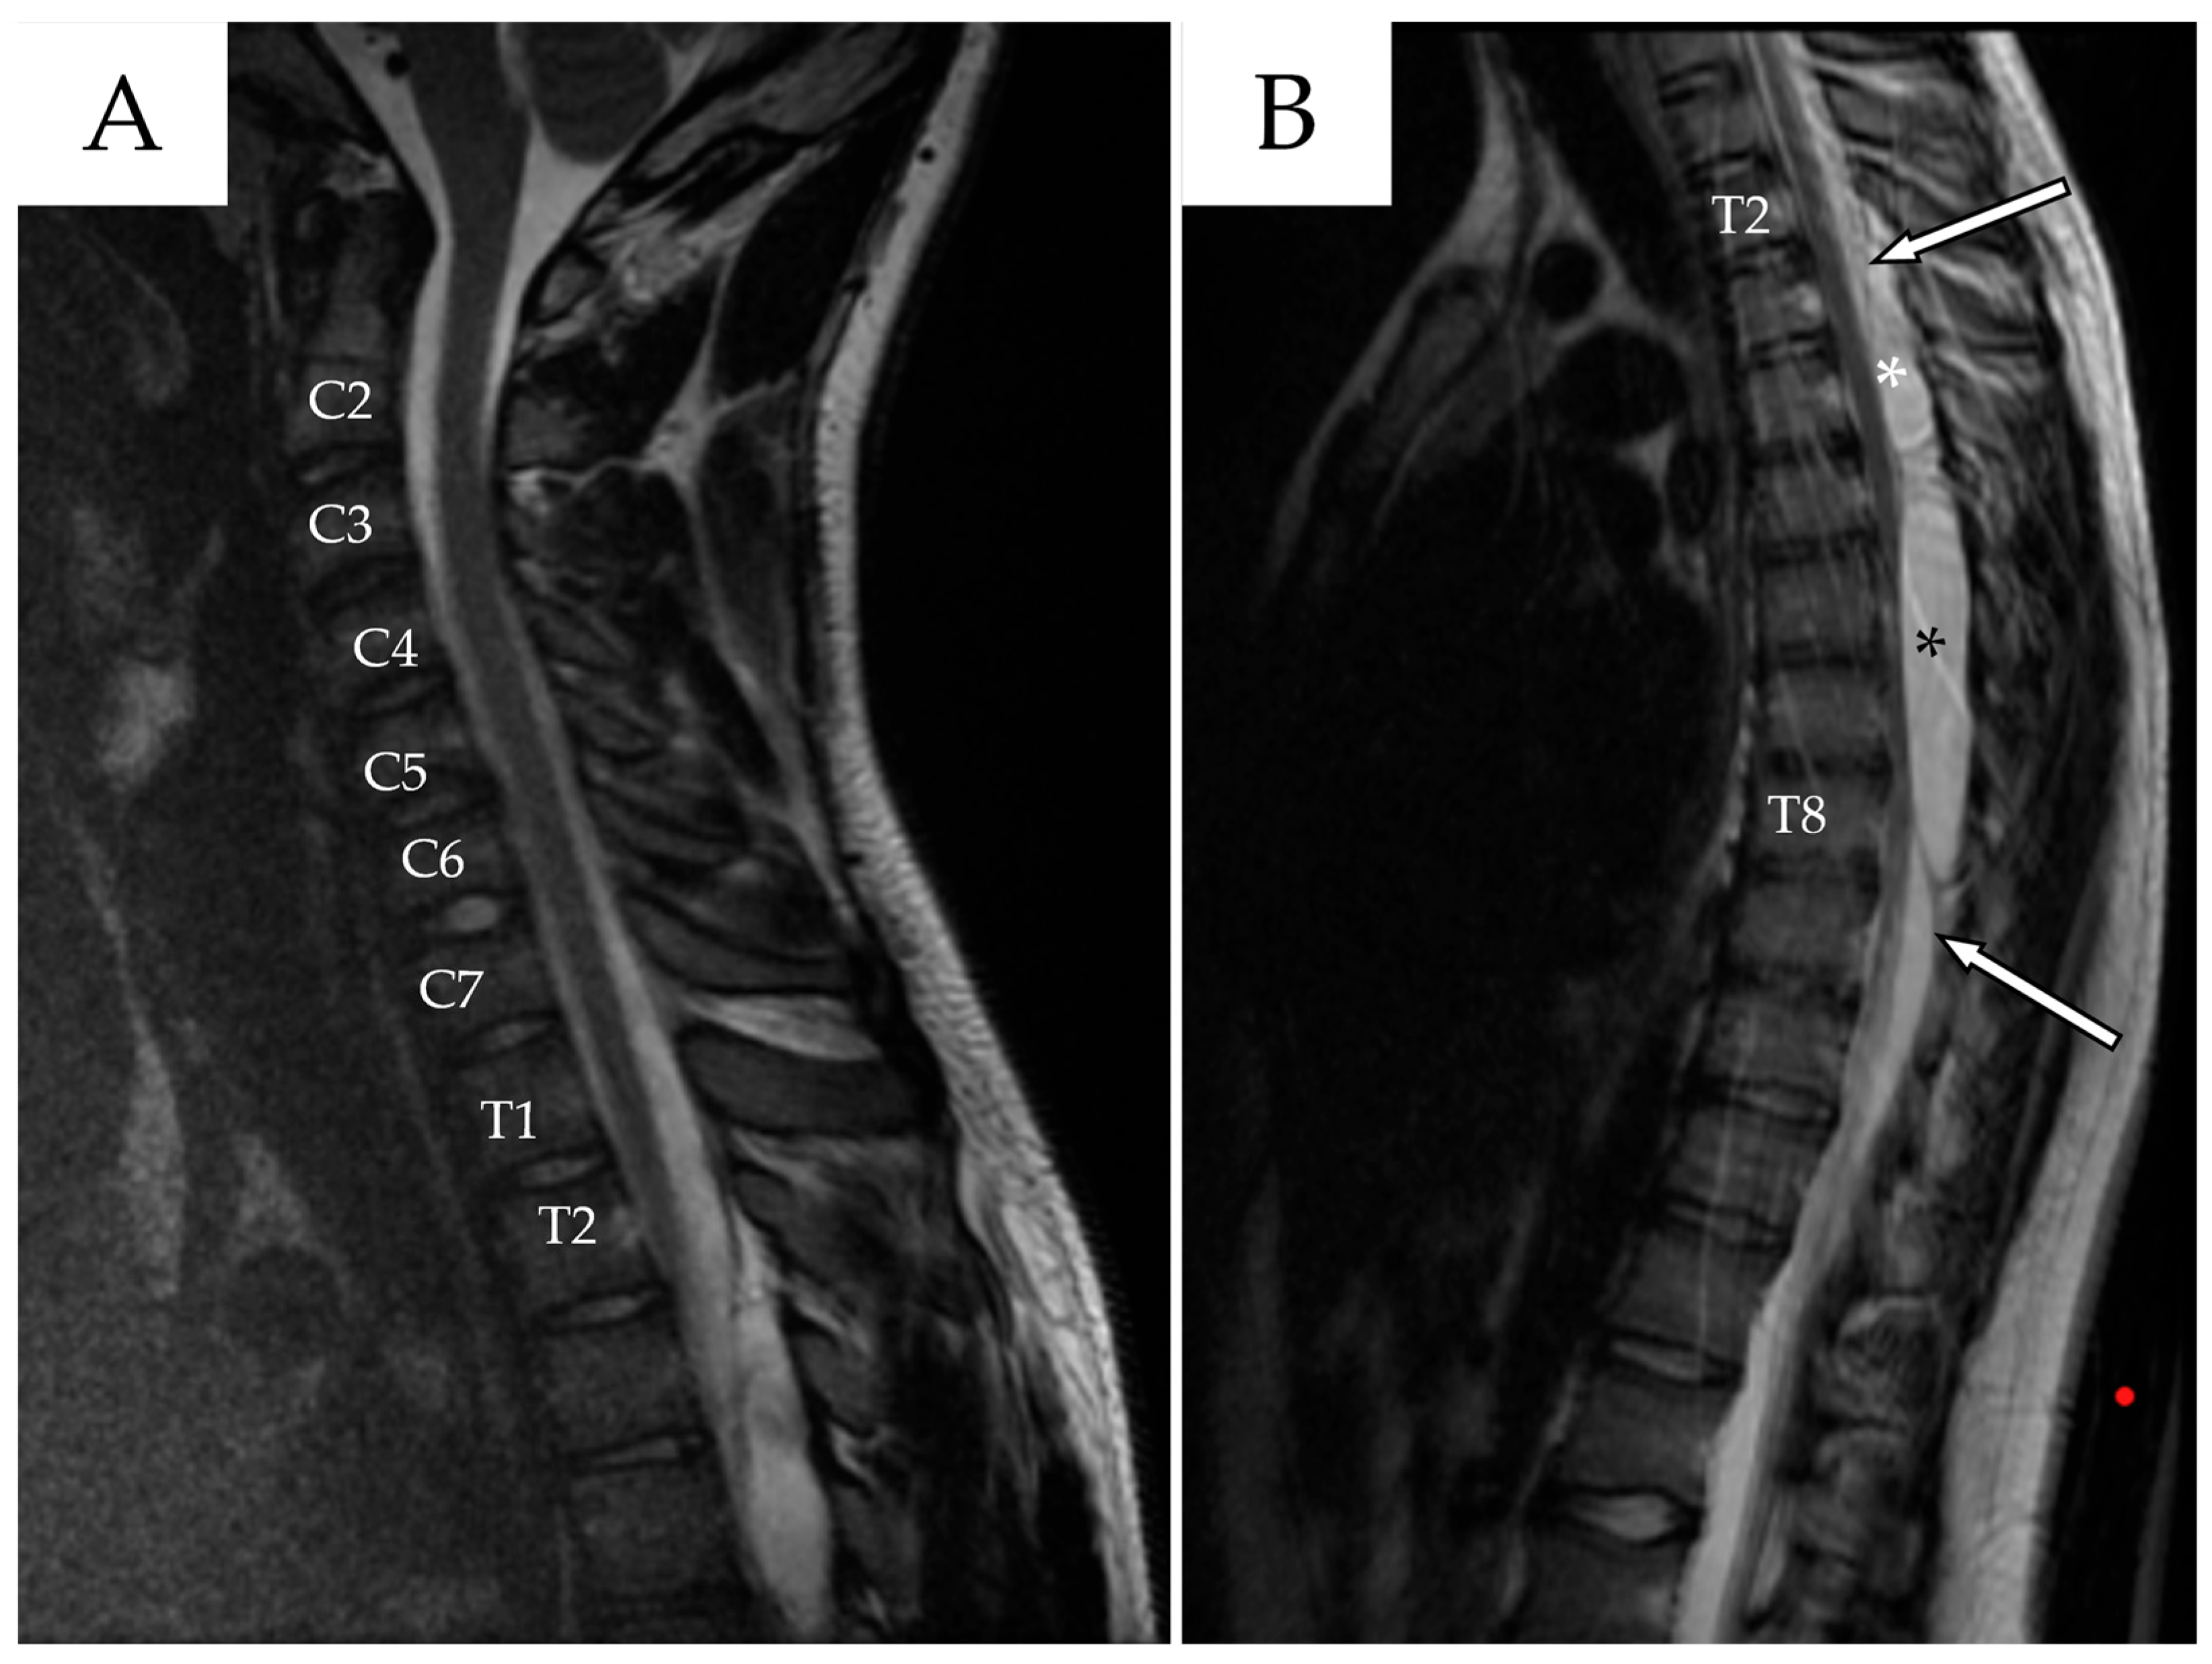

2.1. First Admission

2.2. First Follow-Up

2.3. Second Admission